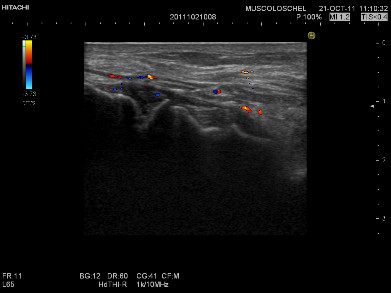

• Ecografia muscolo tendinea e osteoarticolare

• Follow up ecografico delle patologie infiammatorie articolari

• Interventistica ecoguidata dell’apparato muscolo scheletrico: